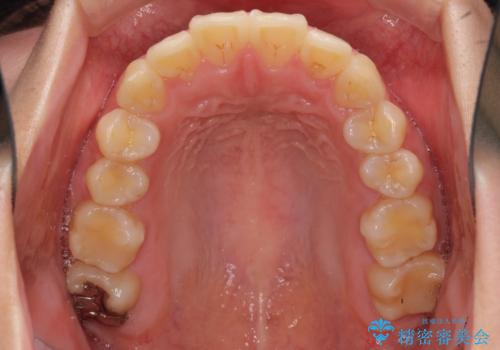

- 上下前歯を部分矯正したところ出っ歯になってしまったとのことで来院された患者様です。

上下左右第一小臼歯4本を抜歯して、積極的に口元を引っ込めるよう、ワイヤー装置にて矯正治療を行うこととしました。

治療後には口が閉じやすくなり、患者様には大変満足していただきました。